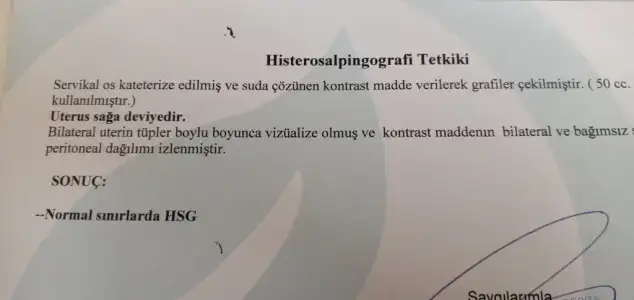

Selam canım, Ben 4 ay oldu Hsg çekildim ve anestesisiz çekildim hatta kendi tercihimdi. Doktor cekti.. Yani aslinda çok abartili bir agri sizi olmuuor ben dayandim ve bittikten sonra oyle yok yureyemiyorum yok agrim oluyor diye bir durumum da olmadi. Sayanabilecekcek hic korkma cektir.. Ultrason gibi alttan muayene gibi dusun. kisiden kisiye gore degisebilir tabiki fakat benim dayanilmayacak kadar acisi olmadi bi baslangicinsa hatta teki kapaliudi tupun acildi. Yani korkma derim kendini rahat birakirsan bol nefes alip verirsen hic bir sıkıntı olmaz korkulacak birsey yok

yeni tecrubem.. bende korkuyordum. anestezi olmadan daha iyi zaten. dayanirsin.